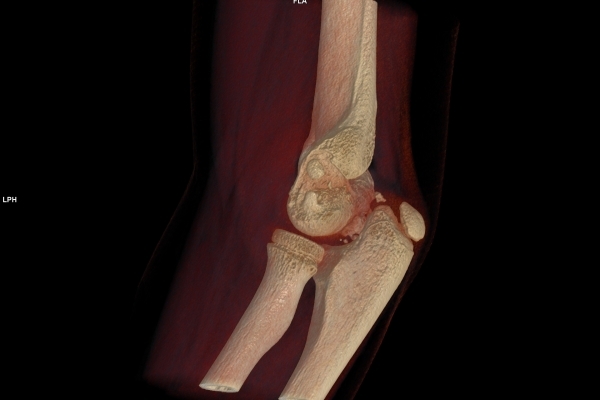

CT Untersuchung Bild

Die MRT (Magnetresonanztomographie) arbeitet mit Magnetfeldern und Radiowellen und eignet sich besonders für Untersuchungen der Weichteile wie Gehirn, Muskeln oder Gelenke. Die CT (Computertomographie) nutzt Röntgenstrahlen und liefert schnelle, hochauflösende Bilder, insbesondere für Knochen, Lunge oder innere Organe. Die Wahl der jeweiligen Untersuchung richtet sich an das individuelle Krankheitsbild und wird bei der Überweisung festgelegt.